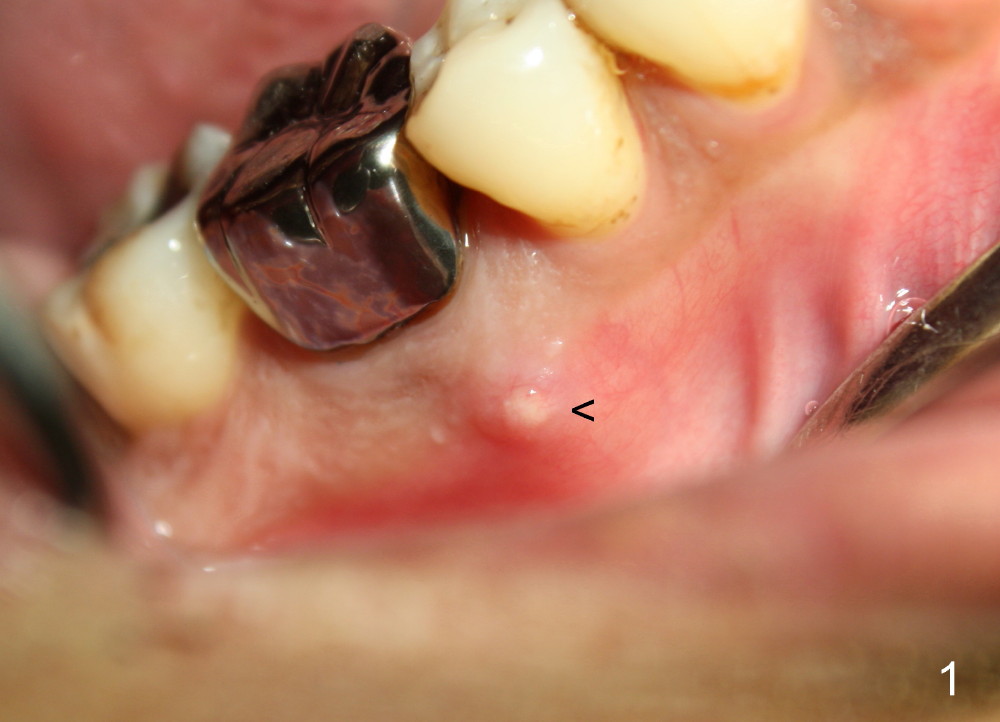

The patient returns for extraction and immediate implant after 7 days of oral Amoxicillin. There is a deep pocket mesiolingually in addition to the mesiobuccal fistula (Fig.1 <). The metal crown and then the tooth are sectioned. The crack of the mesial root is confirmed during extraction. The coronal portion of the mesiobuccal plate is defective, corresponding to the fistula. Both the mesial and distal sockets are large with a thin septum in between. Osteotomy is established at the base of the septum, slightly toward the mesial socket, as evidenced by a 5x20 mm tap in place (Fig.2). Finally, a 7x17 mm implant is placed (Fig.3 I; A: abutment; G: bone graft). The insertion torque is more than 60 Ncm.

Three weeks postop, the gingiva is healthy around the implant (Fig.5 I). There is no symptom or sign of the infection (>, as compared to Fig.1). The abutment has accomplished its transient function (A, the perio dressing having dislodged) and is subsequently removed (Fig.6, to reduce micromovement of the implant and cheek and tongue bite). The 7 mm implant (I) does not look too big in its new home (alveolus). Four months postop, the mesial socket appears to have normal bony trabecular patterns (Fig.7, as compared to Fig.3).